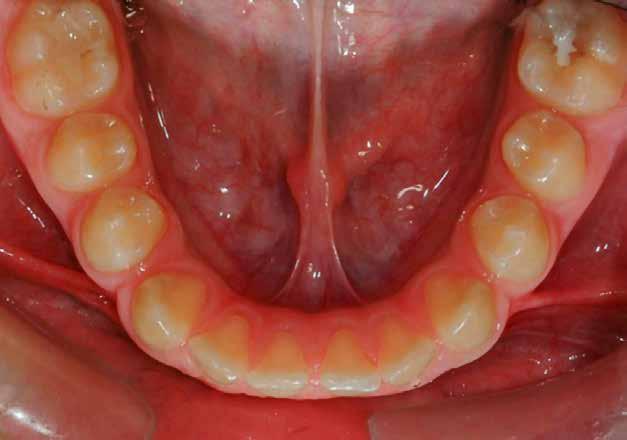

5. Alsó okkluzális (tükör)

Az asszisztens most a kisebb retraktorokat fordított V alakban leengedi, hogy az alsó ajkakat oldalra és a fogaktól távolabb húzza vissza. A klinikus most felfelé

emeli a tükröt, hogy láthatóvá tegye az alsó ív tükörképét, miközben a pácienst arra kéri, hogy „emelje fel kissé az állát”. Ideális esetben a felvétel a tükör síkjához képest 90°-ban készül, úgy, hogy az utolsó jelenlévő zápfog látható legyen. Fontos kérdés lenne itt a páciens nyelvhelyzete a fénykép készítése közben. A legjobb, ha megkérjük a pácienst, hogy „görgesse viszsza” a nyelvét a tükör mögé, hogy az ne zavarja a fogak láthatóságát, különösen a hátsó területen (11. ábra).